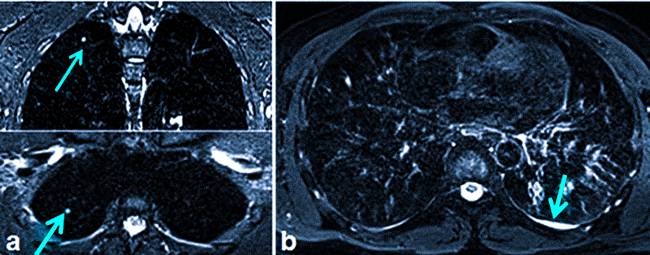

image Туберкулез на снимке МРТ (стрелками показаны очаги в паренхиме легких (а) и туберкулезный плеврит (b))

• диссеминированная форма туберкулеза представлена множественными очагами, которые могут иметь разную форму, в том числе однородную правильную. На снимках МРТ наблюдают распространенность патологических признаков по всем отделам легких;

• туберкулезный плеврит — на изображениях обнаруживают жидкость в грудном отделе, которая часто не отличается от нормального секрета.